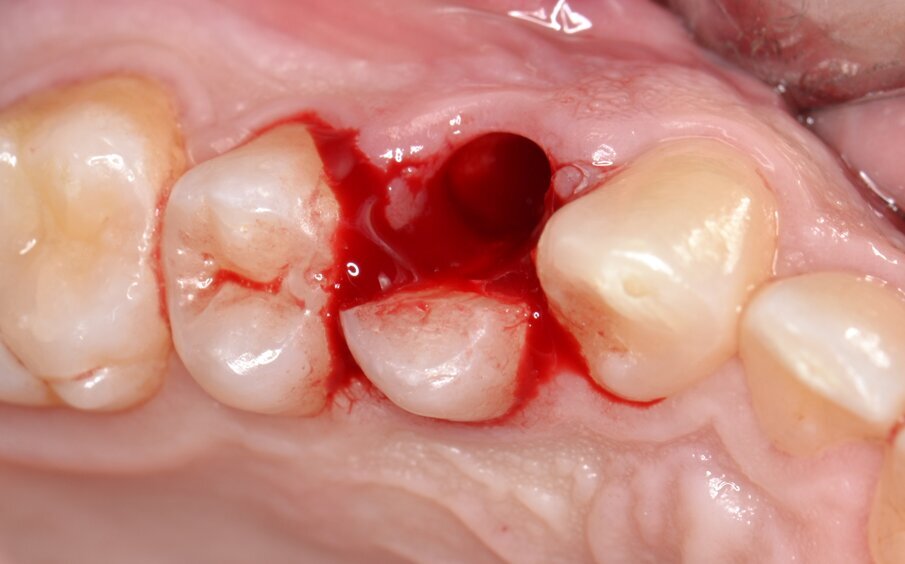

All’esame obiettivo viene si evidenzia una frattura verticale a carico dell’elemento in questione (Figg. 1, 2) che pone indicazione assoluta all’estrazione dentaria; per evitare di aggravare l’inevitabile contrazione della cresta ossea alveolare, si decide di eseguire l’estrazione dell’elemento fratturato senza sollevare alcun lembo. Viene effettuato un esame radiografico endorale allo scopo di visualizzare la morfologia della radice dentaria e i suoi rapporti con le strutture viciniori. (Fig. 3)

Fig. 1 - Elemento 1.4 fratturato (visione occlusale).

Fig. 7 - Alveolo postestrattivo integro.